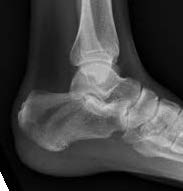

Imaging